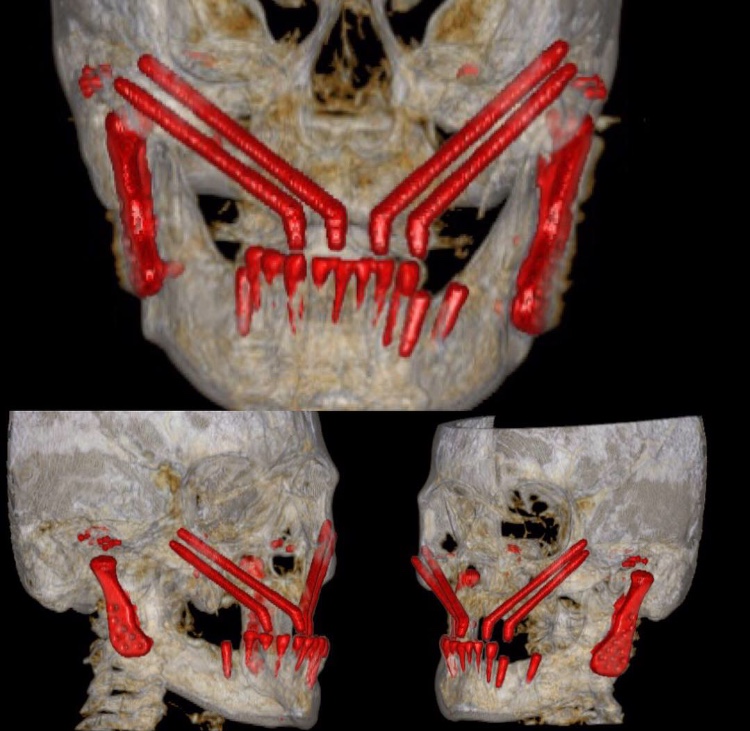

Implantes cigomáticos y rehabilitación dental

Los implantes cigomáticos son una opción para la rehabilitación dental de pacientes con pérdida ósea...